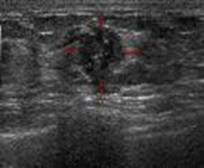

平日健康的女性、當發現有腫塊、乳頭分泌物、出血、乳房疼痛、乳房皮膚凹陷、或是乳頭內凹等症狀時、就可以依不同年齡做乳房攝影或超音波來進行乳癌的篩檢或診斷.目前國健局除補助五十至六十九歲婦女每兩年一次免費乳房攝影篩檢外, 又新增補助國內四十五至四十九歲婦女每年一次免費乳房篩檢.有此疾患之婦女可多加利用。 |